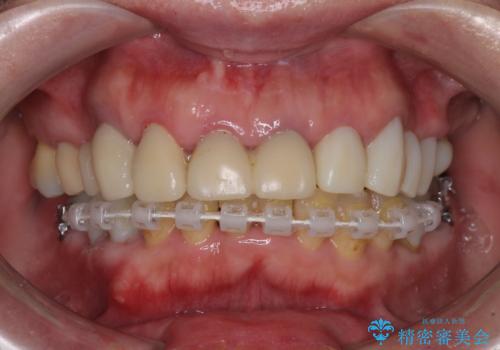

歯肉の状態が落ち着いた後に下顎の矯正治療を行い、その後補綴治療を行うこととしました。